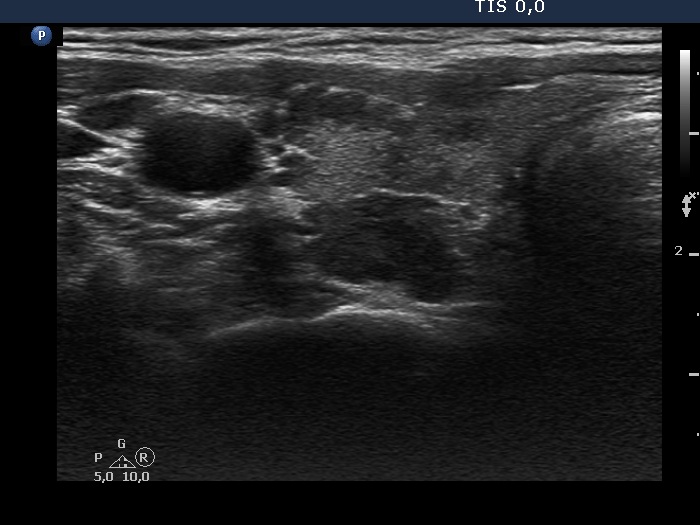

Discrete lesion or nodule in Hashimoto's thyroiditis - case 24 (430) (ultrasonographic picture 4)

Lowest part of the right lobe, transverse view. The dorsal hypoechogenic area has irregular shape and lobulated borders.